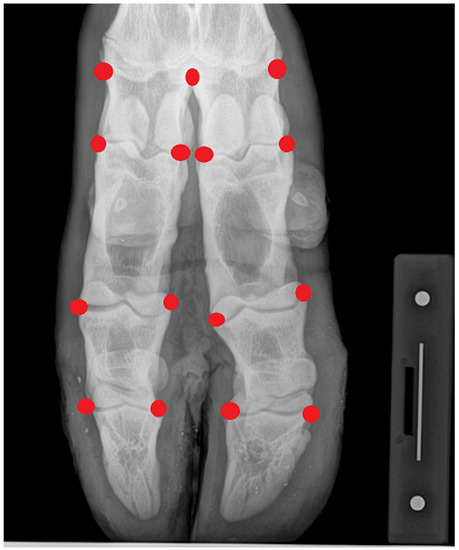

2.2. Imaging

2.3. Statistical Analyses